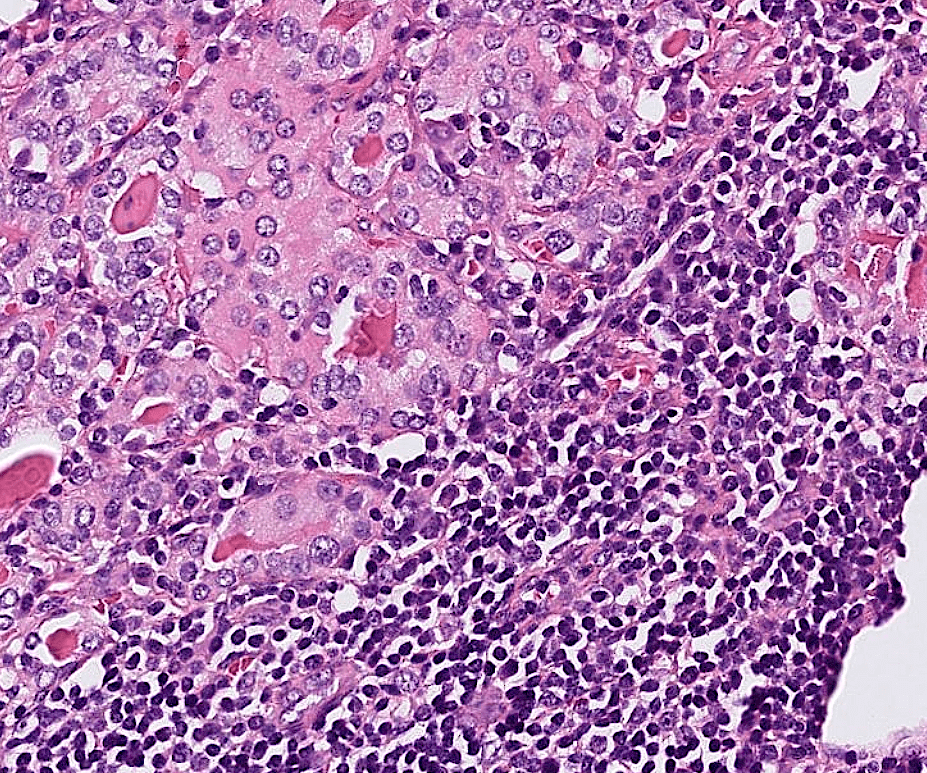

endometrial cancer